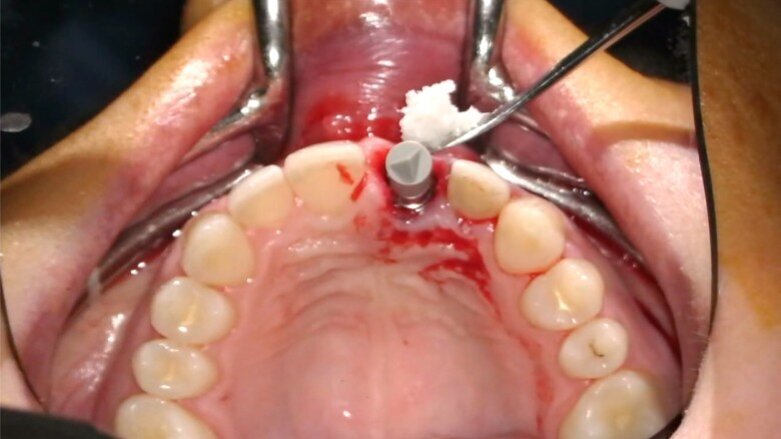

- Personalizzazione matrice “FIBRO-GIDE”

Geistlich Fibro-Gide (Geistlich Pharma) è una matrice in collagene di origine suina, porosa, riassorbibile e volumetricamente stabile, progettata specificatamente per la rigenerazione e l’aumento dei tessuti molli al fine di evitare il prelievo autologo di tessuto connettivo. Tale matrice, usata in guarigione sommersa, favorisce l’angiogenesi, la formazione di nuovo tessuto connettivo e permette la stabilità volumetrica dei tessuti, ripristinando la corretta ampiezza biologica1-11. In un caso estetico come questo, la matrice va personalizzata e adattata al sito ricevente. Essendo molto stabile e mantenendo il suo volume in fase di guarigione non va, infatti, sovradimensionata per evitare trazioni del lembo e/o volumi eccessivi a guarigione avvenuta; non deve essere inoltre eccessivamente compressa dal lembo in modo che possa mantenere la sua originale struttura reticolare interna. Trattandosi di una matrice particolarmente resistente quando asciutta, suggerisco di modellarla utilizzando una fresa in zirconia a bassi giri (KOMET): in tal modo, infatti, si riesce a modellarla in modo preciso, evitando comunque il surriscaldamento e la denaturazione del collagene mantenendo le sue caratteristiche strutturali inalterate (Figg. 20, 21).

Fig. 20_Personalizzazione della matrice collagene.

Fig. 21_Matrice customizzata.